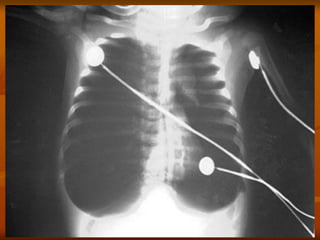

3. X QUANG PHỔI

Có thể BT: 13 % trẻ NV có XQ BT

 DH thường gặp:

 Ứ khí phế nang

 Thâm nhiễm mô kẽ, quanh PQ, PN

 Xẹp phổi: thùy trên phải

 Đông đặc phổi: 24%

 DH hiếm gặp: Tràn khí MP-TK trung thất (1%)

Tràn dịch MP

3. X QUANGPHỔI  Không đặc hiệu: Có thể BT: 13 % trẻ NV có XQ BT  DH thường gặp:  Ứ khí phế nang  Thâm nhiễm mô kẽ, quanh PQ, PN  Xẹp phổi: thùy trên phải  Đông đặc phổi: 24%  DH hiếm gặp: Tràn khí MP-TK trung thất (1%) Tràn dịch MP